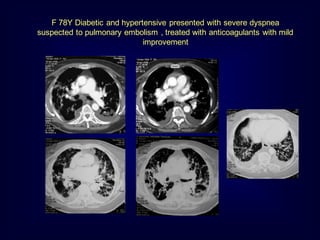

F 78Y Diabetic and hypertensive presented with severe dyspnea

suspected to pulmonary embolism , treated with anticoagulants with mild

improvement

F 78Y Diabeticand hypertensive presented with severe dyspnea suspected to pulmonary embolism , treated with anticoagulants with mild improvement